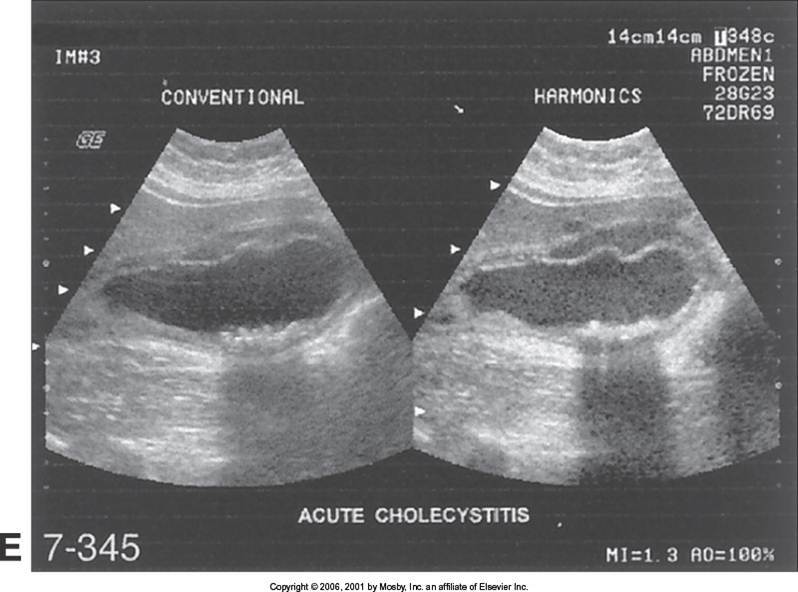

Acute Cholecystitis

Wall Thickening